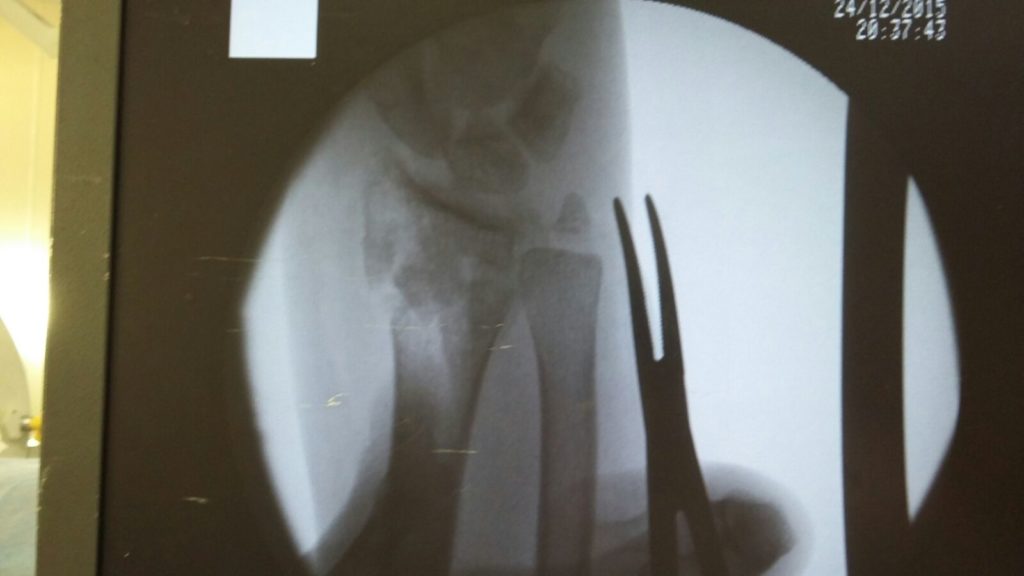

Операция - открытая репозиция, остеосинтез лучевой кости пластиной с костной ксенопластикой материалом "Остеоматрикс". На контрольных снимках в три месяца имеется консолидация перелома, миграции фиксатора нет, имеется остеоинтеграция ксенопластического материала.